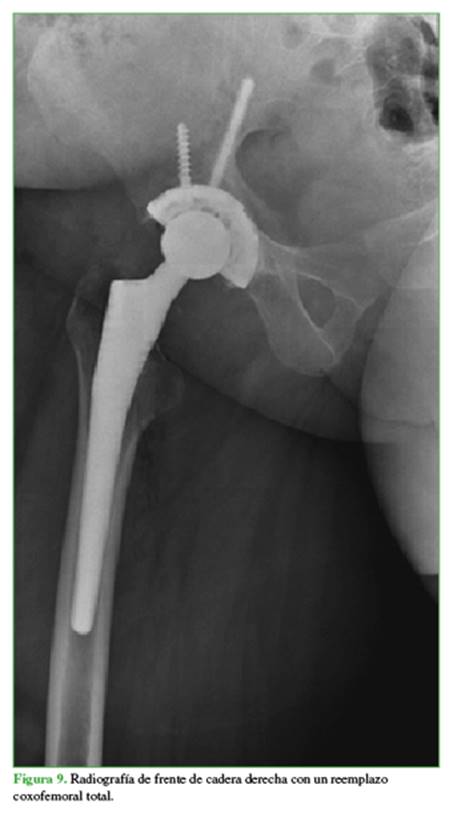

La escasa respuesta al tratamiento médico llevó a indicar un reemplazo total de cadera con limpieza y toma de biopsia intraquirúrgica (Figura 9). Se confirmó el diagnóstico de sinovitis granulomatosa crónica.